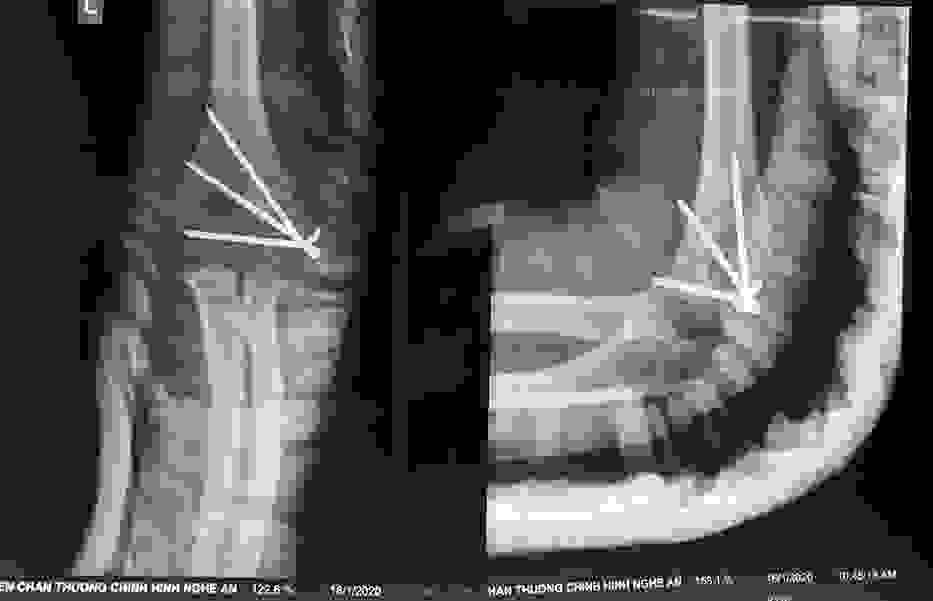

Phẫu thuật thành công ca bệnh hiếm gặp...khớp giả bẩm sinh xương chày

26/06/2019 17:00

Đã xem: 3383

Bệnh viện Chấn thương- Chỉnh hình Nghệ An, vừa phẫu thuật thành công cho bệnh nhi khớp giả bẩm sinh xương chày